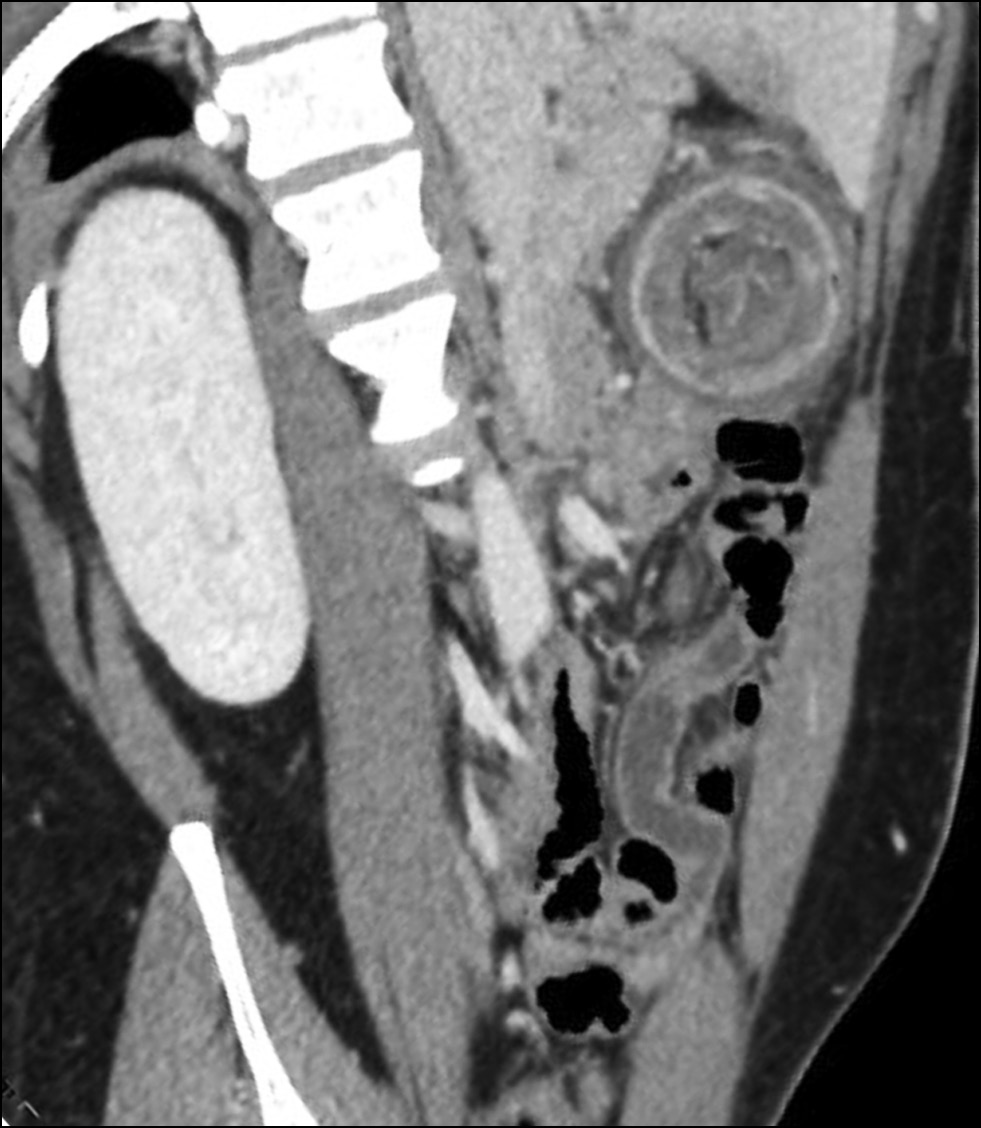

Multiplanar reconstruction (MPR) revealed the “target” appearance of the intestinal walls (Fig. 2).

Fig. 2. Oblique sagittal multiplanar reconstruction, orthogonal to the intussusception, shows the “target sign” due to the alternating of edematous walls and mesenteric fat.